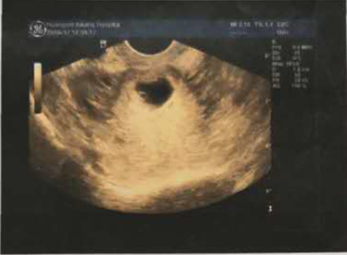

一次意外怀孕,让已有两个孩子的尤女士开心不起来,当经过反复检查核实,确诊为子宫瘢痕妊娠时,她不由得惊慌了起来。

子宫瘢痕妊娠,顾名思义,就是受精卵没有着床在正常的子宫内膜部位,而是着床在上一次剖宫产的切口瘢痕处。危险的是,孕囊着床在瘢痕处,局部血液循环差,不利于胚胎发育,且随着胚胎的长大,极有可能会造成子宫破裂。因此,尤女士本次怀孕必须要终止。

子宫瘢痕处妊娠是较难处理的异常妊娠,也是妇产科医师很头痛的问题之一。因为它的病理机制在于受精卵通过剖宫产后瘢痕组织的裂隙或窦道,侵入瘢痕内并在肌层种植,持续生长,其所形成绒毛与子宫肌层黏连,甚至穿透子宫壁,这也是医学处理的关键难点,治疗上不仅要干干净净清除掉妊娠囊,还需要修复瘢痕缺损,防止复发。